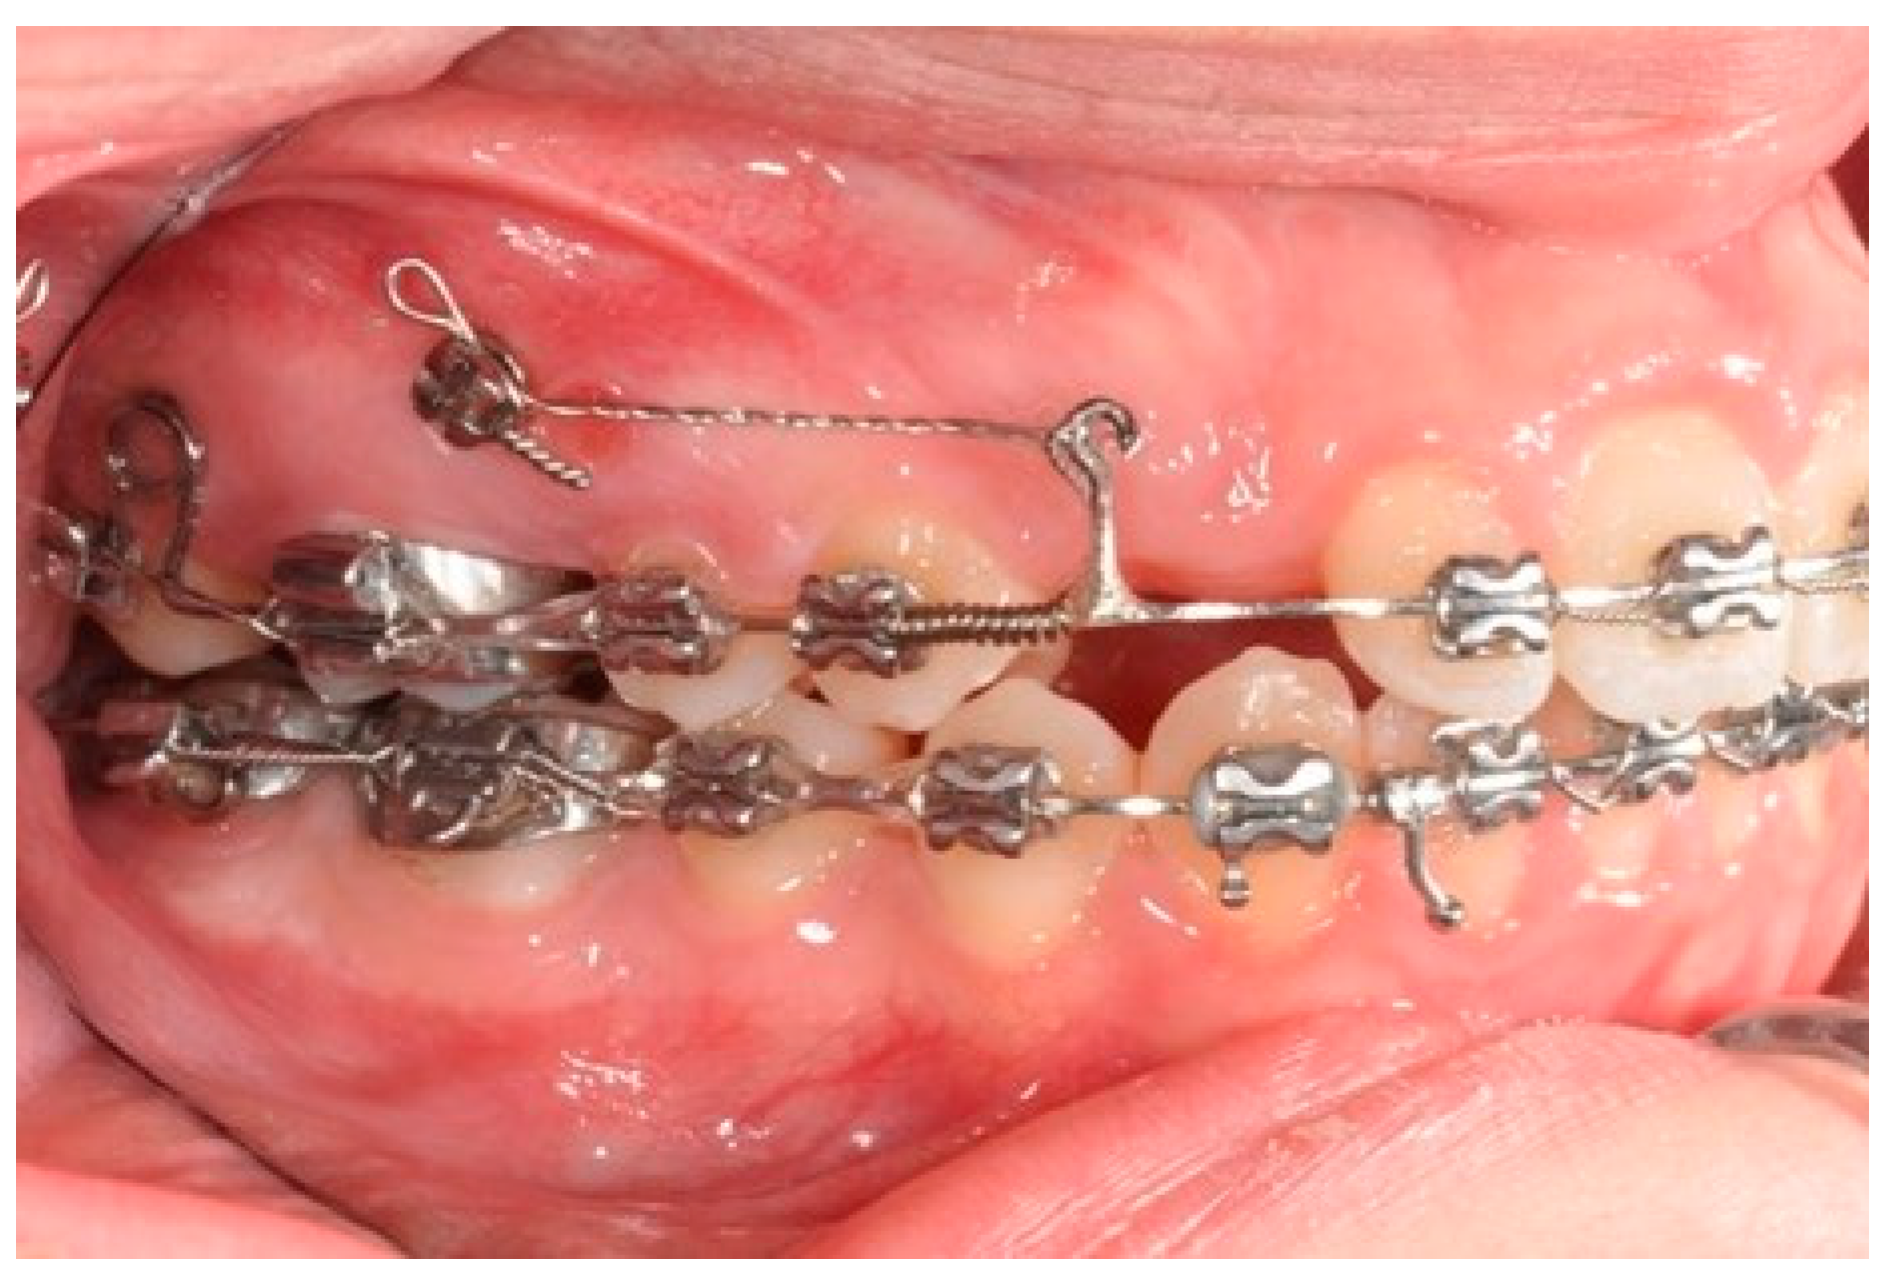

2.2. Molars’ and Premolars’ Distalization